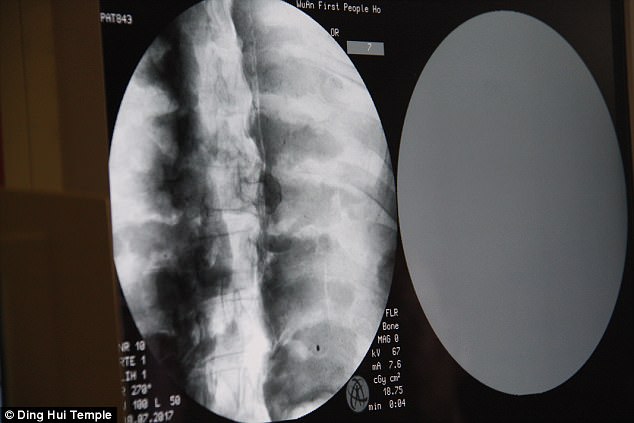

Sự kiện gây chấn động diễn ra vào ngày 8 tháng 7 năm 2017, khi các nhà khoa học tiến hành chụp CT để kiểm tra bên trong "bức tượng" này trước sự chứng kiến của giới truyền thông và đông đảo người dân. Kết quả hình ảnh quét được đã khiến tất cả những người có mặt phải bàng hoàng. Các bác sĩ xác nhận rằng bên dưới lớp mạ vàng, nhà sư Ci Xian vẫn giữ được bộ xương nguyên vẹn cùng một bộ não hoàn chỉnh.

Kết quả hình ảnh từ máy quét đã khiến toàn bộ giới khoa học và những người chứng kiến phải kinh ngạc đến mức sững sờ. Các bác sĩ xác nhận rằng nhà sư Ci Xian vẫn còn giữ được một bộ xương hoàn chỉnh cùng một bộ não nguyên vẹn.

Bác sĩ Wu Yongqing, người trực tiếp tham gia buổi kiểm tra cho biết xương của ngài khỏe mạnh và rõ ràng như một người bình thường. Từ xương hàm trên, răng, xương sườn, xương sống cho đến tất cả các khớp đều vẫn còn nguyên vẹn một cách khó tin. Sự tồn tại hoàn hảo của thi hài sau hơn 1.000 năm đã chứng minh kỹ thuật ướp xác đỉnh cao thời bấy giờ, tạo nên một hiện tượng chấn động khiến cả thế giới phải chú ý.

Những hình ảnh có được sau khi chụp CT